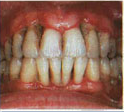

Periodontitis caused because of retained calculus manifested as gingival recession and pocket formation. Bone levels are also affected.

Stage 4

Advanced Periodontitis in which bone loss is severe causing mobility of teeth and gingival recession.